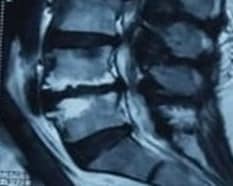

After obtaining informed consent, the patient was taken to the operating theatre. Antibiotics were administered by peripheral venous access to prevent infection before intradiscal PRP injection. PRP was made by the department of transfusion medicine, ShSMCH, and the platelet count was more than 1000000/ml. The patient was placed in a prone position on the X-ray operating table, and the L4-5 level was identified by counting vertebrae from X-ray images. With all aseptic precautions, the skin was infiltrated with 1% lignocaine. Then, a spinal needle (22-gauge, 150mm) was inserted into the nucleus pulposus (NP) of the L4/5 disc in the anteroposterior (AP) and lateral views under intermittent fluoroscopy. Approximately 2 mL of PRP was slowly injected through a syringe into the disc. After the procedure, the patient was observed in the post-operative ward for about an hour and found uneventful. The patient was advised to do activities of daily living and physical activity, such as exercise, at 7 days and 1 month postinjection, respectively. She was also advised not to take steroids and non-steroidal anti-inflammatory drugs (NSAIDs) for about 1 month, except in the case of particularly severe pain (VAS scores of 8 points or more). Follow-up surveys, including VAS, RMDQ, and any side effects, were carried out by phone at 1 week, 1 month, 3 months, 6 months, and 12 months following intradiscal PRP injections. Quality of life by SF-12 was measured after 1 month, 6 months, and 12 months. Subsequently, a follow-up MRI of the lumbar spine was done after 6 months of injection. Figure 1 shows the Modic change before and after PRP injection. A decrease in high signal intensity on T2WI was seen after PRP injection in the intervertebral disc at the L4/5 disc.

MRI shows modic change before (a,b) and after (c,d) PRP injection

Figure 1: MRI shows modic change before (a,b) and after (c,d) PRP injection

The process of Modic change in our patient was somehow reversed by PRP injection. This autologous platelet-rich plasma mimics the physiological repair process by releasing autologous growth factors (GFs) and creating a transient biological matrix. It can be considered that PRP treatment could stimulate the endogenous repair machinery and induce the healing of damaged spinal components to ultimately restore disc and vertebral bone homeostasis and an improvement in the functional anatomy of the end plate.[20] It is difficult to determine whether Modic type 1 is the cause of LBP. Discography may be necessary to diagnose Modic change accurately as the cause of LBP. However, discography, an invasive test, was not performed in this study because a significant association was established between MC and LBP.[25]

Only a few reports demonstrate MRI improvements in disc degeneration and Modic change after PRP treatment. As MRI provides more detailed information, the case presented here shows appreciable MRI improvements in terms of decreasing high-signal intensity on T2WI after 6 months of PRP therapy.[20,25] Other modalities like intradiscal steroid injections, anti-tumor necrosis factor (TNF)-α antibodies, and antibiotic administration, have been reported to have short-term efficacy in Modic change, but long-term results are unknown. Albert et al. treated patients with Modic type I with antibiotics for 100 days and reported that the VAS of patients with LBP improved from 67 to 37 mm after 1 year.[27]